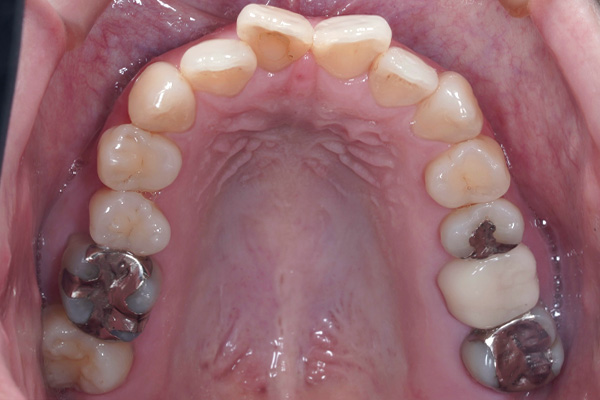

従来の歯列矯正はワイヤーを使用して行う治療でしたが、マウスピース矯正は透明なマウスピースを使用して行う矯正治療になります。世の中からワイヤー矯正がなくなることはありませんが、マウスピース矯正のシェアが世界中で増えてきているのは事実です。パソコン上で歯の動きをシュミレーション出来ることが大きな利点となります。最初の計画通り矯正治療が進んでいるのか治療の途中で進み具合のチェックも可能になります。

当院では全ての患者様にインビザライン治療を行うことはしていません。それは、インビザライン矯正、ワイヤー矯正、ワイヤー矯正とインビザライン矯正のハイブリッド矯正の中で最善な方法で矯正治療を行っているからです。もちろん患者様のご要望を考慮して治療方針を計画します。それぞれのシステムには利点と欠点が存在すると考えていますので、患者様の口腔内の状態でどのように治療を行っていくのか診査・診断を行い治療方針の決定をしていきます。

現在のインビザラインは治療の適応範囲が非常に広がり、システム上は全ての方に使用することができます。しかし、咬み合わせによってはワイヤー矯正のほうが良いこともあります。患者様のご要望と当院の診断結果をもとに話し合いをさせて頂き治療方針を決定していきます。

軽度の歯の叢生(歯の並びがデコボコ)の患者様、歯の動かす量が少なく治療できる患者様になります。

全ての患者様が適応になります。